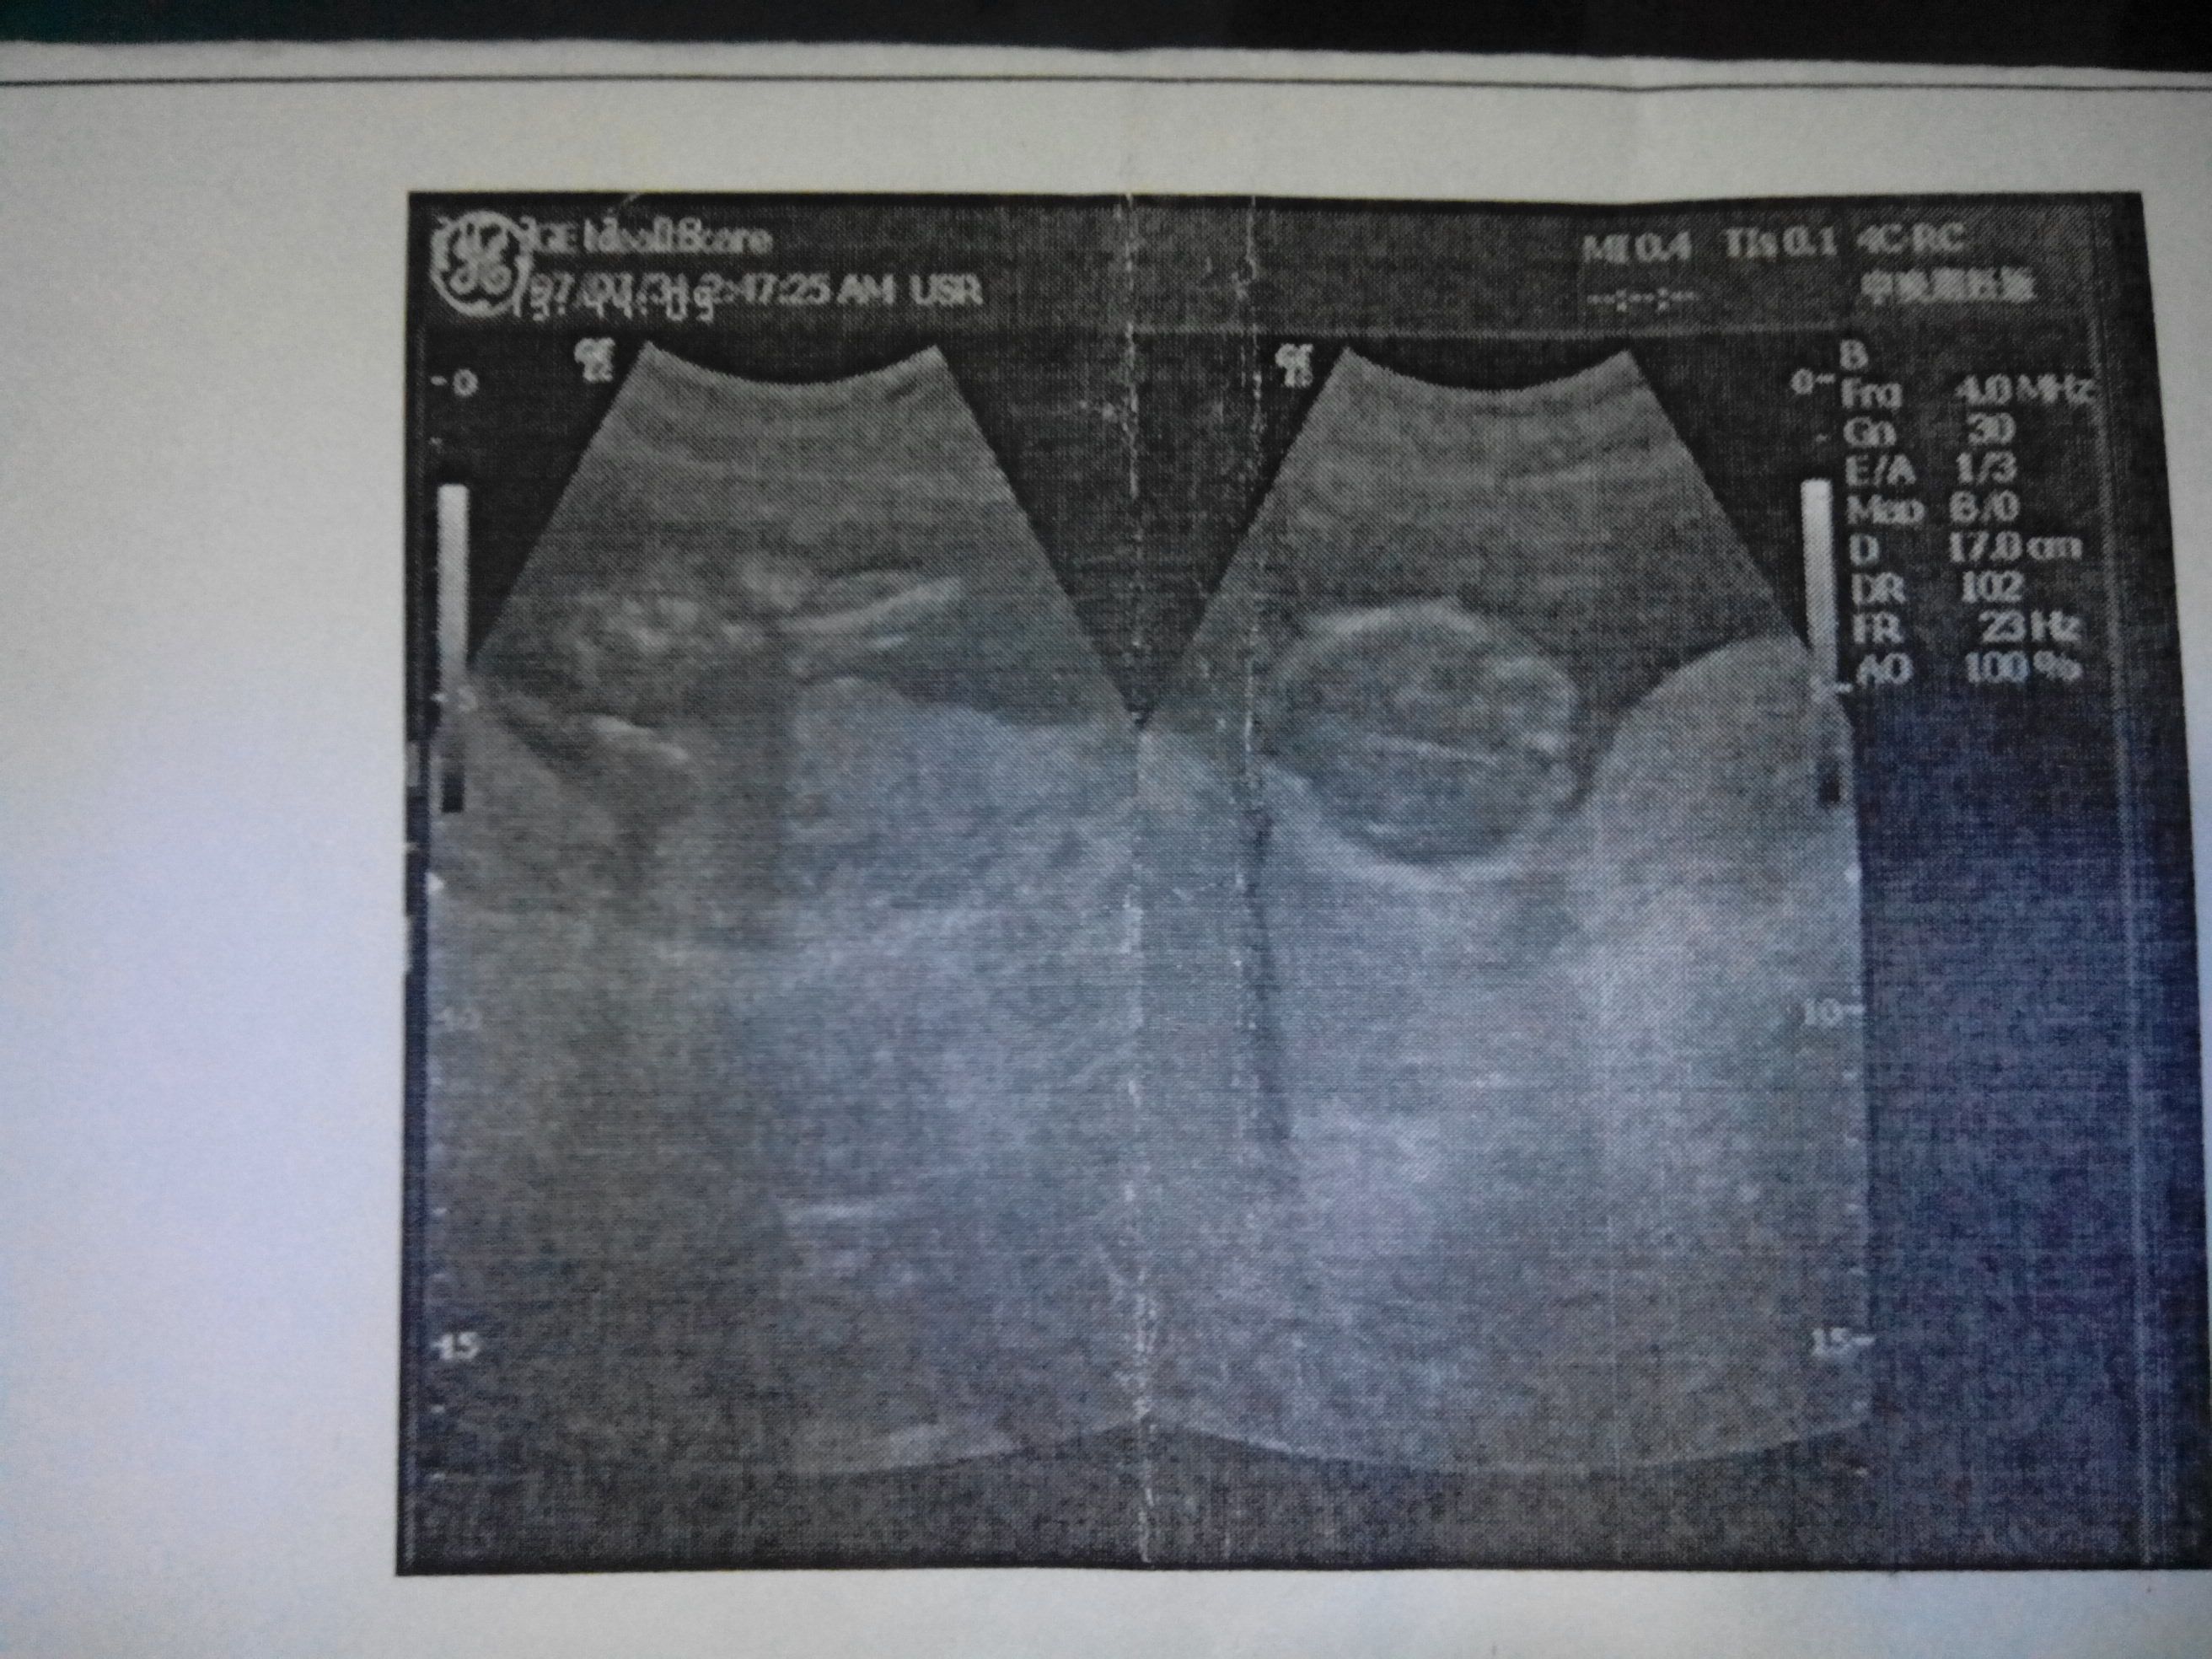

来位高手看看我的宝宝是男孩还是女孩

因为我有一个女儿了,想要个儿子啊

我猜是男孩,人说男孩是脸朝外背对着妈妈,女孩是脸朝里抱着妈妈。我看B超宝宝是脸朝外的